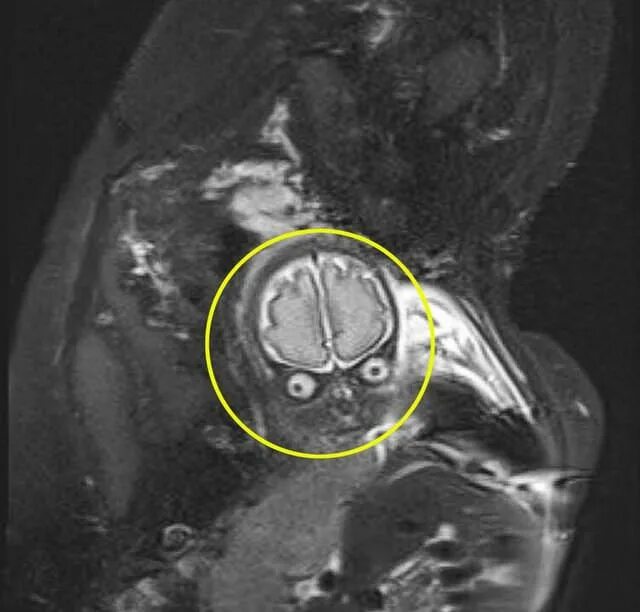

Делала рентген при беременности